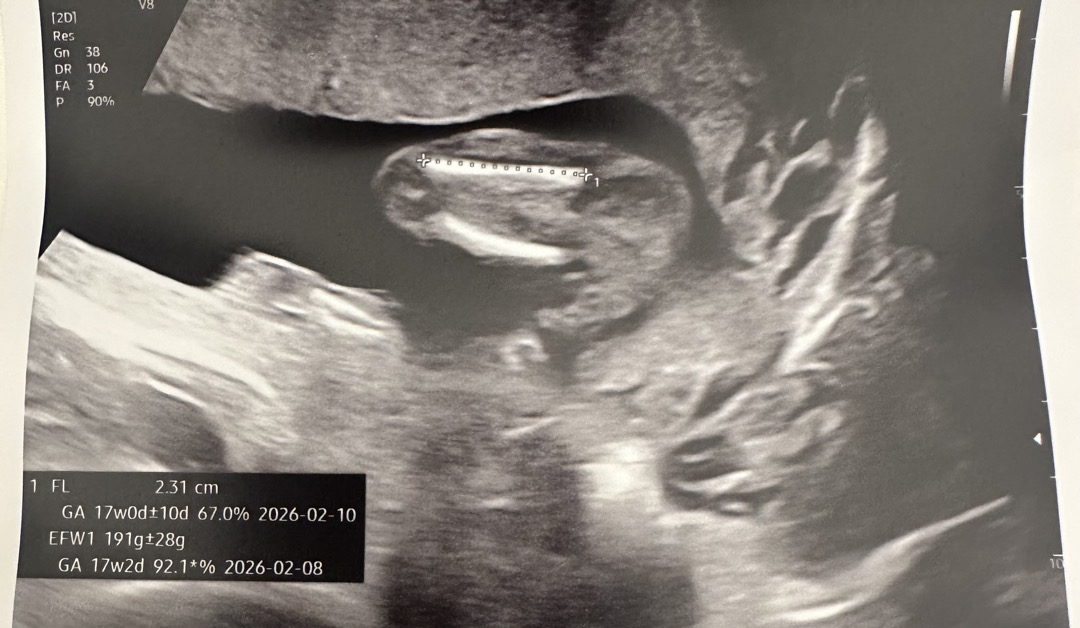

저는 아직 초음파 사진 봐도 잘 모르겠더라구요. 의사샘이 아래 사진으로 아들이라고 알려주셨는데 니프티 검사 결과지에도 성별은 안나와있고… 혹시 사진 상으로 뭘보고 남아라고 판독하셨을까요? 뭐가 보이시나요?

생식기부분이 약간 보이는데요??

보이세요? 다리 사이라고 하셨는데 제 눈에는 다리 한쪽밖에 안보여서요 ;; 두번 설명해 주셨는데도 긴가민가해서 ^^;;

동그란거 보이지않아요?? 그게 생식기 부분같아서요! 현17주찬데 제 아들도 동그란거 보였었어요

ㅎㅎ 그러셨어요? 신기하네요 저는 동그란게 보이긴 하는데 그게 여러군데가 보여서요~~ 다른 초음파 사진을 많이 보면 어느정도 비교가 좀 될 것 같기도 해요 😅